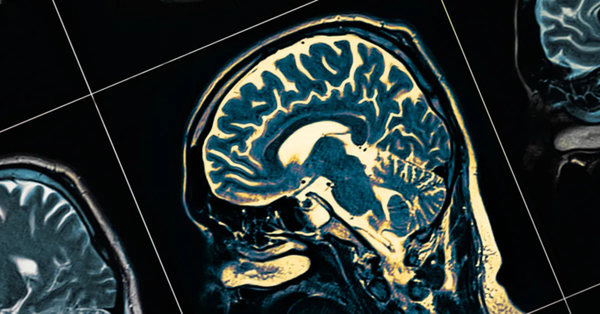

Düzce Üniversitesi Tıp Fakültesi Nöroloji Anabilim Dalı Öğretim Üyesi Doç. Dr. Mehmet Hamamcı, Multipl Skleroz (MS) hastalığına ilişkin önemli bilgiler paylaştı.

Hastalığın ortaya çıkışında genetik ve çevresel faktörlerin karmaşık bir etkileşiminin söz konusu olduğunu ifade eden Hamamcı, "MS doğrudan bir ebeveynden çocuğa geçen kalıtsal bir hastalık değildir; ancak genetik bir yatkınlık zemini vardır. Yatkınlığa sahip kişilerde D vitamini eksikliği, bazı viral enfeksiyonlar ve özellikle sigara kullanımı gibi çevresel tetikleyiciler eklendiğinde hastalık süreci başlayabilir" diye konuştu.

Hastalığın her bireyde farklı şekillerde ortaya çıkabildiğini, bu yüzden zaman zaman "bin bir suratlı hastalık" olarak da anıldığını dile getiren Doç. Dr. Hamamcı, "Ancak en sık karşılaştığımız ilk belirtiler arasında; bir gözde ani görme kaybı veya bulanık görme, kol veya bacaklarda uyuşma, karıncalanma, güç kaybı, dengesizlik, çift görme ve açıklanamayan aşırı yorgunluk hali yer alır" dedi.

Nörolojide "zaman beyindir" yaklaşımıyla hareket ettiklerini kaydeden Doç. Dr. Mehmet Hamamcı, "Erken başvuru ve sıkı takip, hastanın gelecekteki bağımsızlığının ve yaşam kalitesinin en büyük garantisidir. Bu yüzden hastamız bize akut bir atak (ani görme kaybı, güç kaybı vb.) ile başvurduğunda, atağa yönelik tedaviye hemen başlarız. Amacımız, o andaki hasarı en kısa sürede durdurmak ve mümkünse tamamen geriye döndürmektir. Diğer taraftan, MS'in belirtileri başka birçok hastalıkla benzerlik gösterebilir. Bu nedenle 'kesin MS' diyebilmek için, o şikâyetlere yol açabilecek diğer tüm hastalık ihtimallerini tek tek incelememiz gerekir. Hastanın uzun süre kullanacağı koruyucu ilaçlara karar vermek için MS tanısının netleşmesi şarttır. Bu aşamada bazen zaman alan, çok titiz bir 'ayırıcı tanı' süreci yürütürüz. Bu nedenle hastalarımızın belirtileri fark ettikleri anda bize başvurması hayati önem taşır. Çünkü biz, bir yandan hastamıza acil tedavisini verirken, diğer yandan ayırıcı tanı sürecini başlatmak isteriz. Eğer bir hastamız başvurduğunda uluslararası tanı kriterlerini henüz karşılamıyorsa, onu yakın takip sürecine alıyoruz. Böylece süreci en başından kontrol altında tutarak kalıcı hasar oluşmadan müdahale etme şansı yakalıyoruz. Özetle; bir yandan hastamızın şikâyetlerini acil olarak dindirmeye çalışırken, diğer yandan akademik bir titizlikle en doğru tanı ve koruyucu ilaçlara karar vermeye çalışıyoruz" diye belirtti.